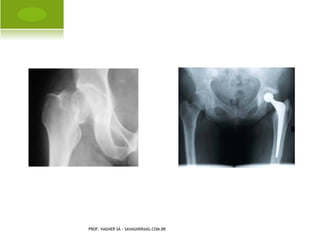

A RTROSE QUADRIL

A RTROPLASTIA PARCIAL

PROF. VAGNER SÁ - SAVAGNER@IG.COM.BR

A RTROPLASTIA TOTAL